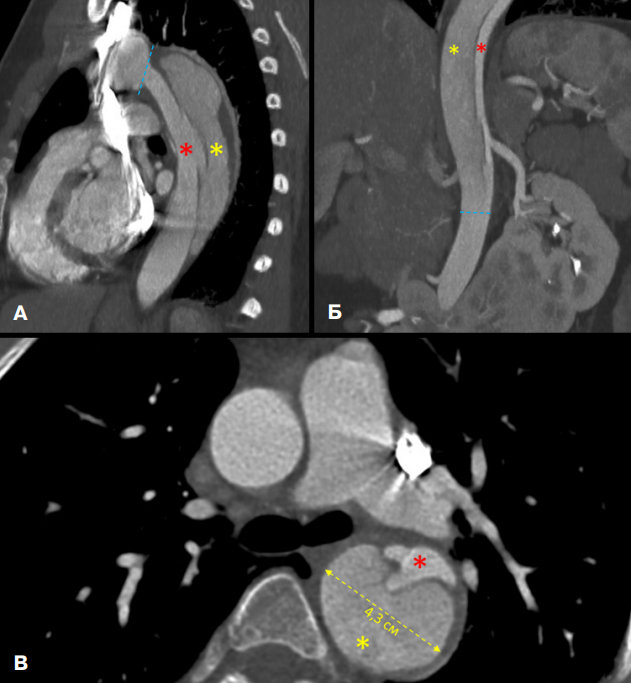

- Представлен клинический случай 32-летней пациентки с генетически верифицированным синдромом Шерешевского-Тернера и развившимся расслоением аорты тип III по DeBakey, подтвержденный данными инструментальных и лабораторных исследований.

Введение. Синдром Шерешевского-Тернера (сШ-Т) представляет собой генетическую патологию, обусловленную полной или частичной моносомией по X-хромосоме. Для данного заболевания характерен полиморфизм врожденных пороков развития, с преимущественным вовлечением эндокринной и сердечно-сосудистой систем. Пациенты с сШ-Т демонстрируют более высокие показатели заболеваемости и смертности в сравнении с общей популяцией, что диктует необходимость комплексного междисциплинарного подхода к их ведению.

Краткое описание. В статье представлен клинический случай пациентки с генетически подтвержденным сШ-Т (кариотип 45,X), у которой прижизненно диагностировано осложнение — расслоение аорты (тип III по Дебейки), что стало возможным благодаря комплексному обследованию. В работе детально описаны характерные фенотипические проявления, особенности клинической картины и течения заболевания, анализ факторов риска, примененные методы лабораторной и инструментальной диагностики и подходы к лечебной тактике.

Дискуссия. Ключевой задачей ведения пациентов с врожденными генетическими заболеваниями соединительной ткани является поддержание высокого уровня клинической настороженности среди врачей всех специальностей. Критически важным представляется не только осознание специфических рисков, ассоциированных с генетическим синдромом, но и тщательная оценка потенциальных триггерных факторов, способных спровоцировать острое сосудистое событие. Оперативное предположение и верификация жизнеугрожающих состояний, к числу которых относится расслоение аорты, определяют выбор неотложной лечебной тактики и могут предотвратить летальный исход.